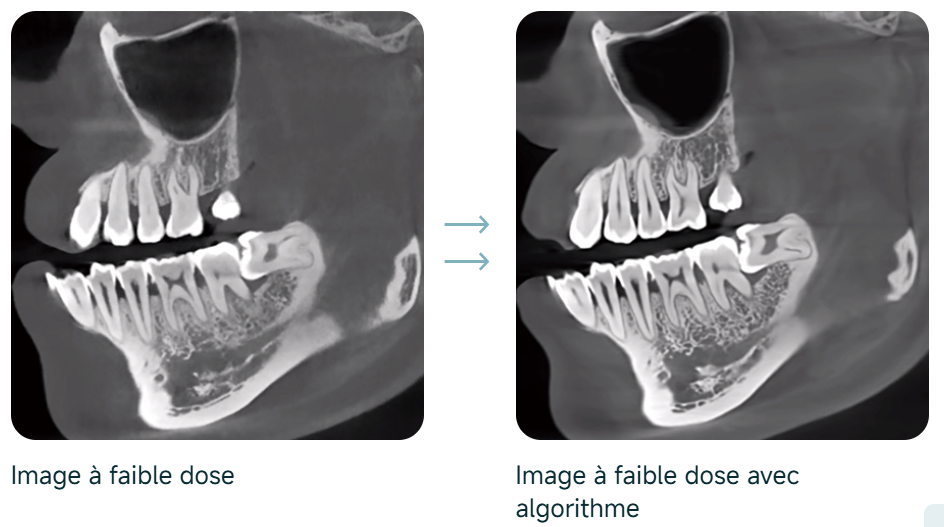

Suppression dynamique du bruit

Dose de rayons X ultra-faible et haute qualité d’image